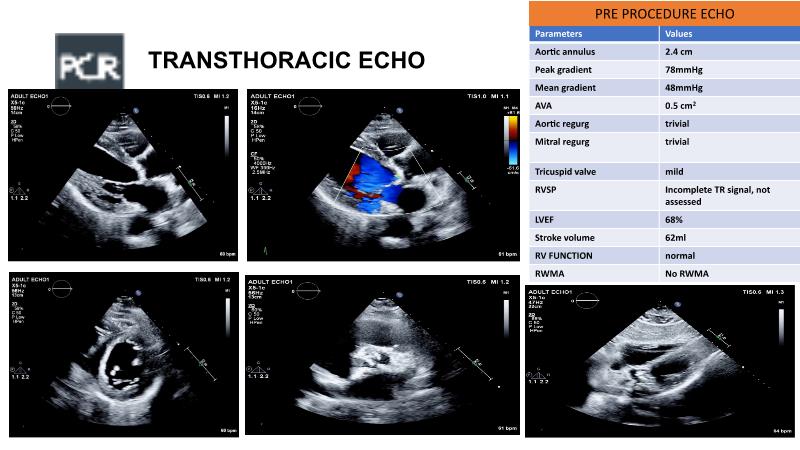

This session with a LIVE case provides information about the Octacor transcatheter heart valve technology, highlighting its procedural and clinical benefits. It also covers the Octalign technique, which ensures precise alignment of commissural and coronary access, and discusses the precise sizing, positioning, and deployment of Octacor THV.